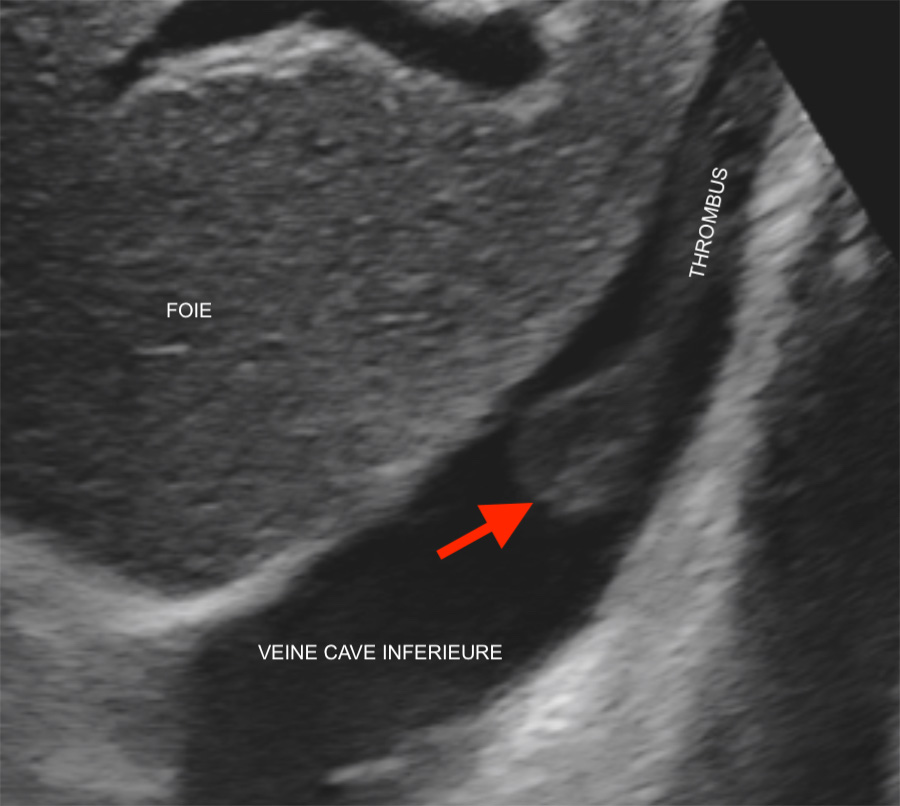

Ecoulement sanguin dans une veine en doppler et codage couleur du sens de l’écoulement